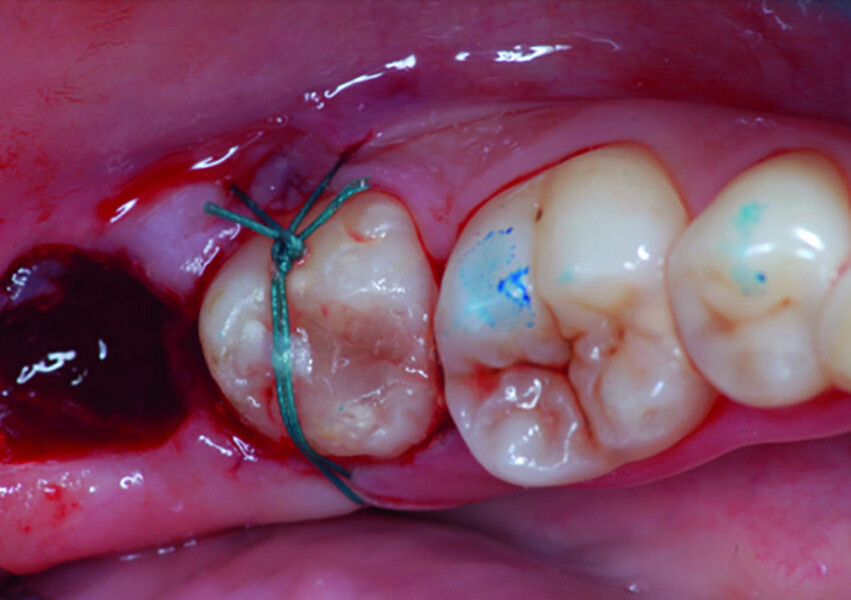

Fig. 8: Transplanted tooth sutured, immediately after surgery.